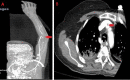

Since the coronavirus (COVID-19) pandemic started, new challenges have emerged regarding the management of coronavirus-infected patients. One of the most known devastating complications associated with COVID-19 is hypercoagulability. This can lead to severe disability or even death, especially in critically ill patients with known chronic comorbidities such as hypertension (HTN) and diabetes. D-dimer and clinical condition are among the most important tools currently used by clinicians to guide therapy and anticoagulation prophylaxis. Here we present a case of a COVID-19-infected patient with no known comorbidities and mild elevation in initial D-dimer level who had a rapid deterioration ultimately leading to death within weeks of admission.